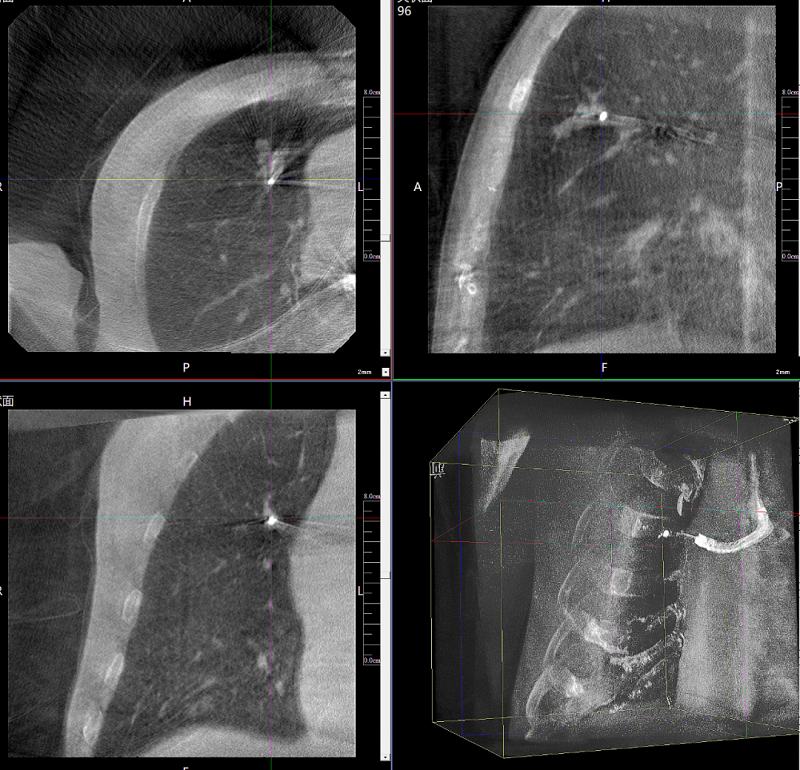

病例3:超聲支氣管鏡下肺活檢(80歲)

三維C形臂還可以創(chuàng)新性地應(yīng)用在呼吸介入領(lǐng)域。例如,在經(jīng)皮穿刺或經(jīng)支氣管鏡肺結(jié)節(jié)活檢、定位、消融等場(chǎng)景中,用于確認(rèn)工具是否到達(dá)病灶、消融范圍是否完全覆蓋病灶等。

二維影像無法準(zhǔn)確判斷工具是否到達(dá)病灶

三維各切面影像都顯示工具達(dá)到病灶內(nèi)